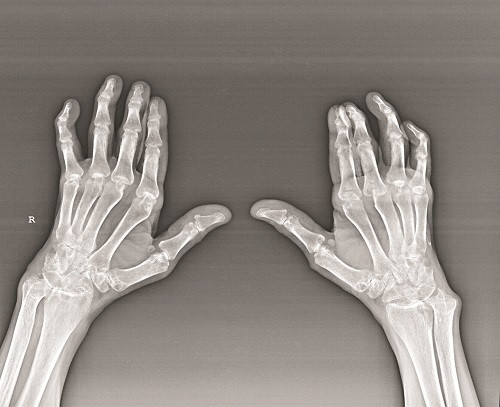

Xét nghiệm sẽ thấy tốc độ máu lắng, tỉ lệ CRP (C- Reactive Protein) tăng cao, đặc biệt là yếu tố dạng thấp RF (Rheumatoid Factor) dương tính. Chụp X-quang thấy có hình ảnh biến đổi xương (mất vôi, hình dải hoặc xói mòn hoặc khuyết xương hoặc hẹp khe khớp hoặc dính khớp.

Chụp X-quang thấy có hình ảnh biến đổi xương